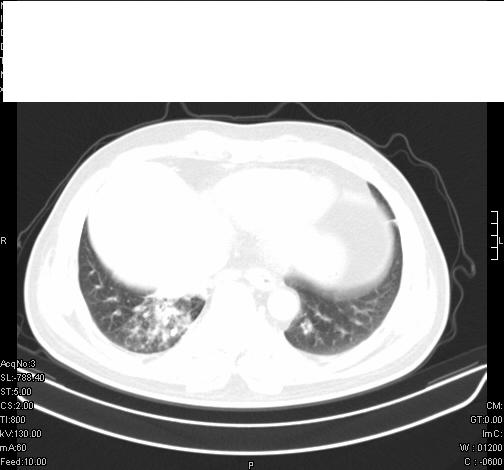

前几天,发了患者的平扫片,患者抗炎一周后增强扫描。右中叶病灶吸收明显,但下叶病灶未见明显吸收。右肺门可见结节影,看来凶多吉少

右肺下叶支气管管腔狭窄,管壁增厚,右下肺见斑片状高密度影,考虑右侧肺门中心肺癌伴阻塞性肺炎

右肺下叶散在的斑片状致密影,下叶支气管变窄。考虑:右肺慢性炎症。

第18幅,好像不能简单用炎症解释,前几天我发平扫时,90%人支持肺癌,现在好像大家更倾向于炎症了,我觉得还是不能排除肺癌。

右肺下叶支气管壁明显增厚,考虑癌症并阻塞性炎症、肺门淋巴结肿大

考虑右肺癌并阻塞性炎症、肺门淋巴结肿大

右肺下叶支气管壁不规则增厚,右肺下叶有斑片状影分布。考虑右肺中央型肺癌伴右肺下叶阻塞性改变。建议支纤镜检查。平扫比增强较好显示了病变情况。

右主支气管狭窄,管壁增厚。考虑右中心性肺ca伴阻塞性肺炎。

既然抗炎治疗有效,可继续治疗;右肺下叶支气管管腔狭窄,管壁增厚,右下肺见斑片状高密度影,右侧主支气管后见结节影(淋巴结?),肺癌不能排出。